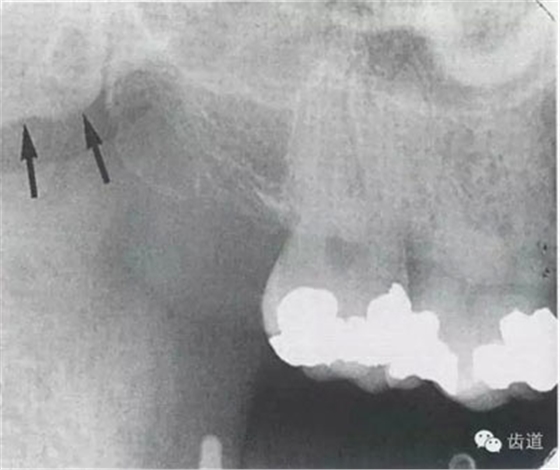

4)外斜線:

由升支前緣下部斜向前下方,為一密度高的帶狀影像。常重疊在第二、三磨牙牙冠處、頸部或根部,使牙髓室或根管不能清晰顯示